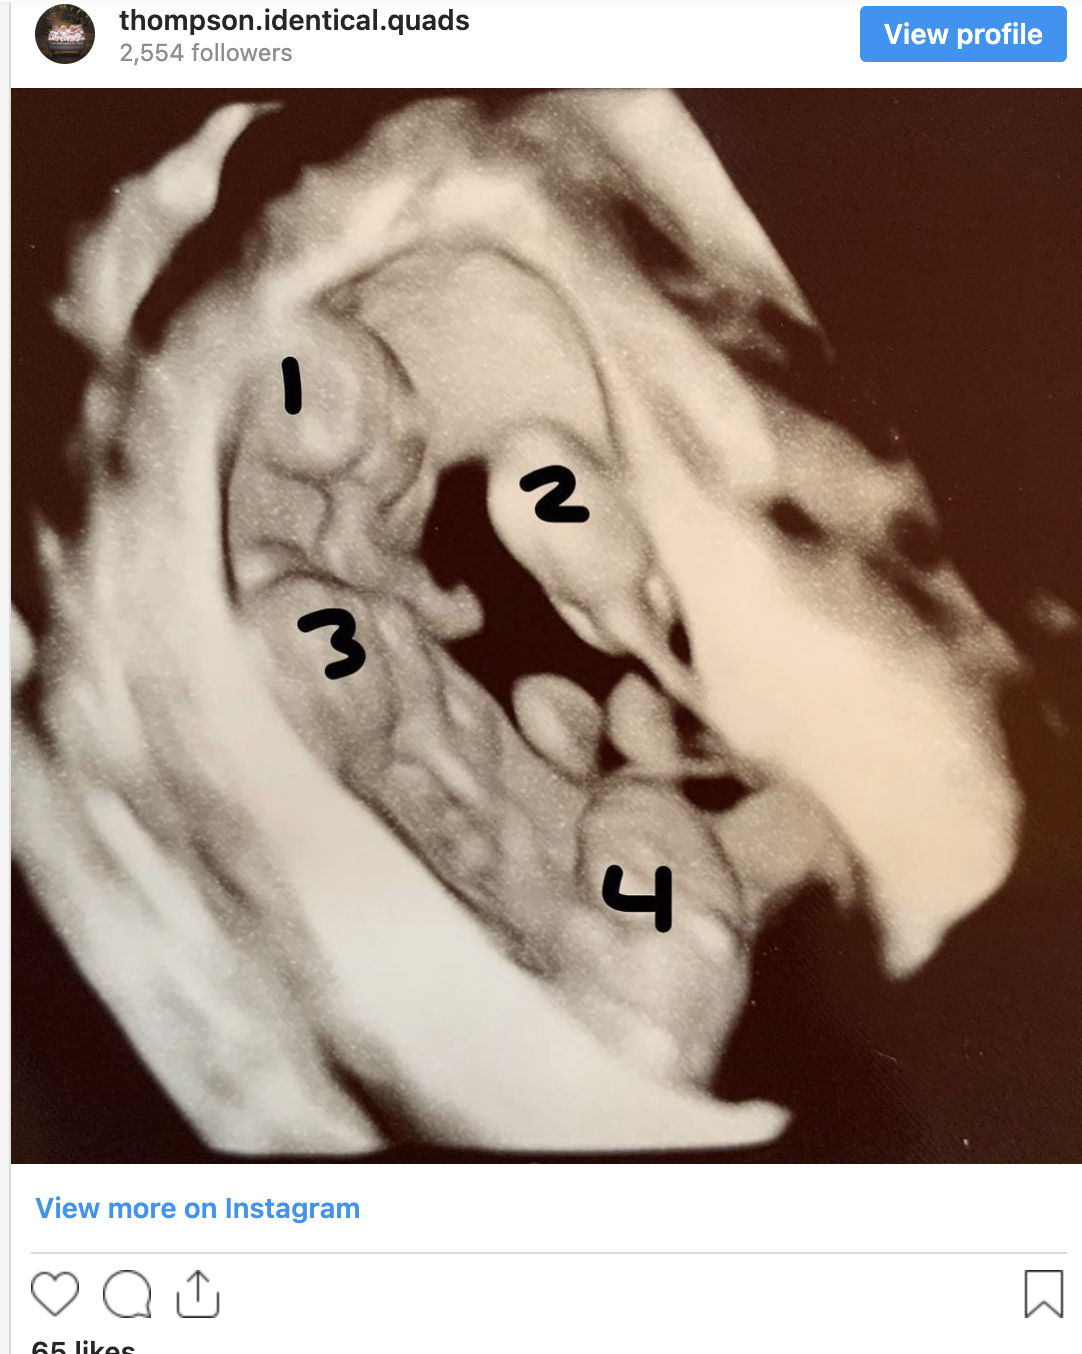

Taylor gave birth to their new set of bundles of joy. They were four little princesses named, Lakely, Sawyer, Kennedy, and Aurora.

What surprised them the most was when they found out their newborn baby girls are all identical!

Having identical quadruplets is rare, it only happens once in 15 million births!